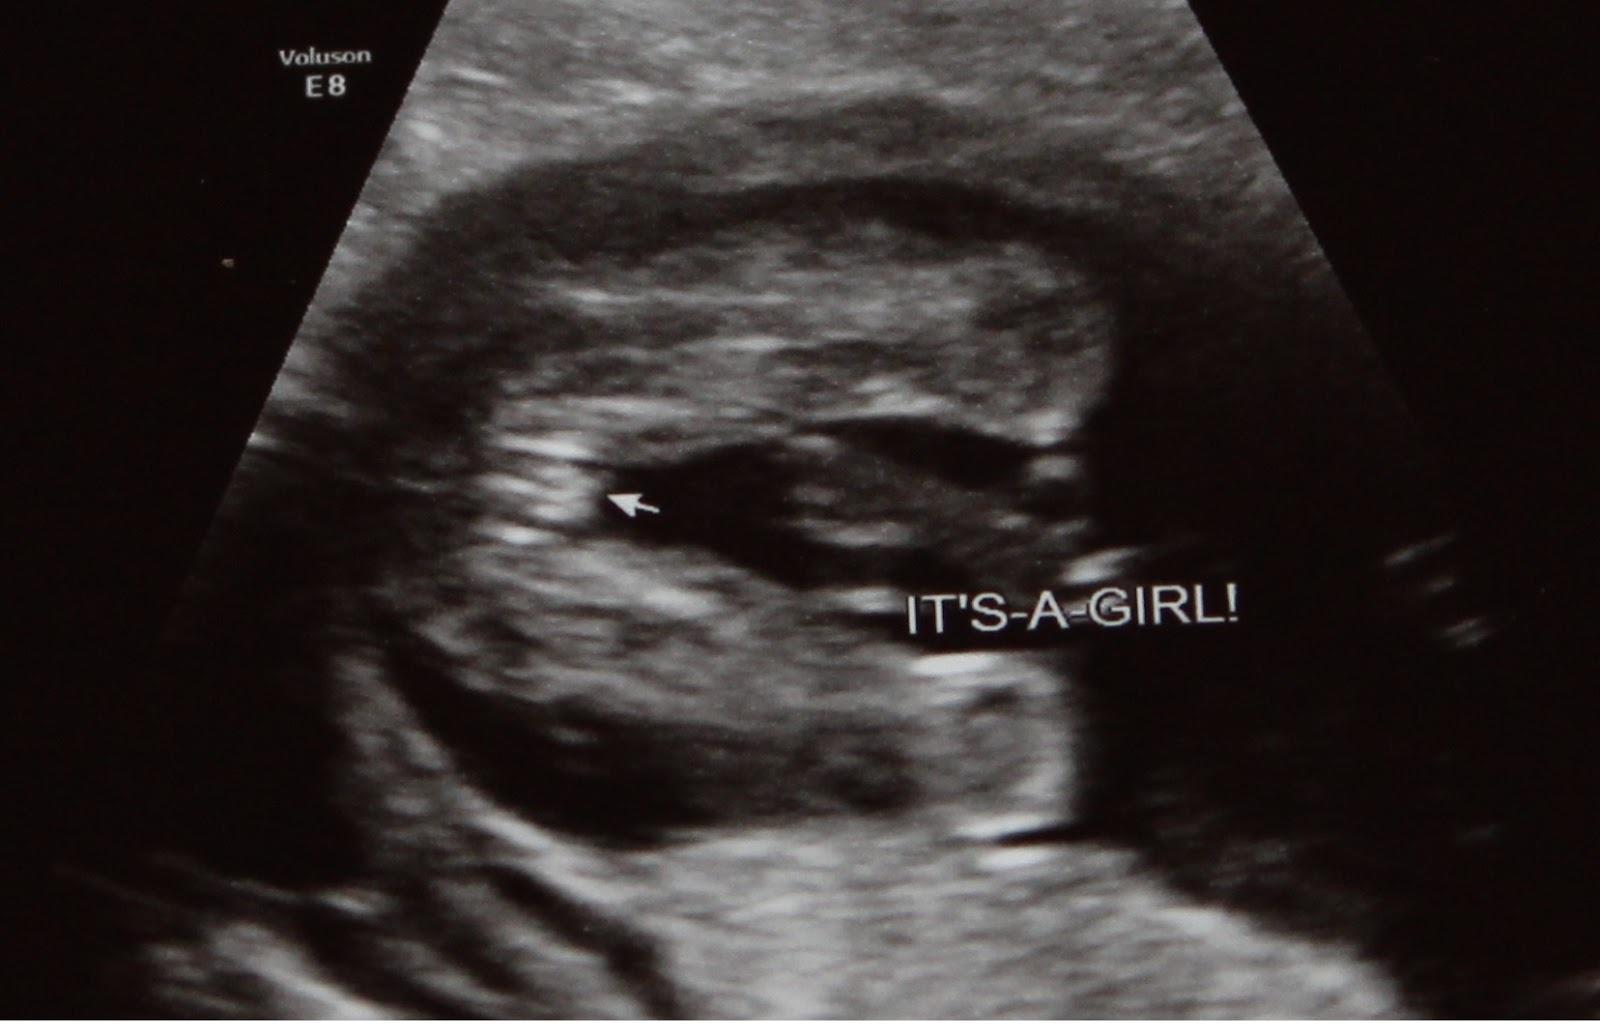

Its revolutionary 3d ultrasound service is offered at 28 canadian locations with 17 years of experience. Send your gender reveal invitations. While those scheduled late in the first trimester (between weeks 11 and 14) get it right about 75 percent of the time, those done in the second trimester have an almost 100 percent accuracy rate, though no test is perfect. Maybe a smile, maybe a. Dna tests, fetal heart rate, chinese gender chart, the drano test, and more.

We'll send periodic pregnancy news, and of course upcoming sales and events. Oct 22, 2021 · hamburger sign: Remember to ask them to show you exactly what they are looking at. The second or third trimester ultrasound can more accurately predict sex. See your unborn child and its tiny features as early as 6 weeks into pregnancy. Sign up and stay in the know! Dna tests, fetal heart rate, chinese gender chart, the drano test, and more. While those scheduled late in the first trimester (between weeks 11 and 14) get it right about 75 percent of the time, those done in the second trimester have an almost 100 percent accuracy rate, though no test is perfect.

See your unborn child and its tiny features as early as 6 weeks into pregnancy. While those scheduled late in the first trimester (between weeks 11 and 14) get it right about 75 percent of the time, those done in the second trimester have an almost 100 percent accuracy rate, though no test is perfect. Sep 07, 2021 · how accurate is a gender ultrasound? Oct 22, 2021 · hamburger sign: The second or third trimester ultrasound can more accurately predict sex. Maybe a smile, maybe a. Sign up and stay in the know! Odds of having another boy or girl.